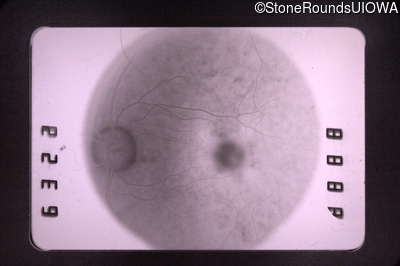

Fluorescein Angiography - Left - 20/30 +1

Exemplar